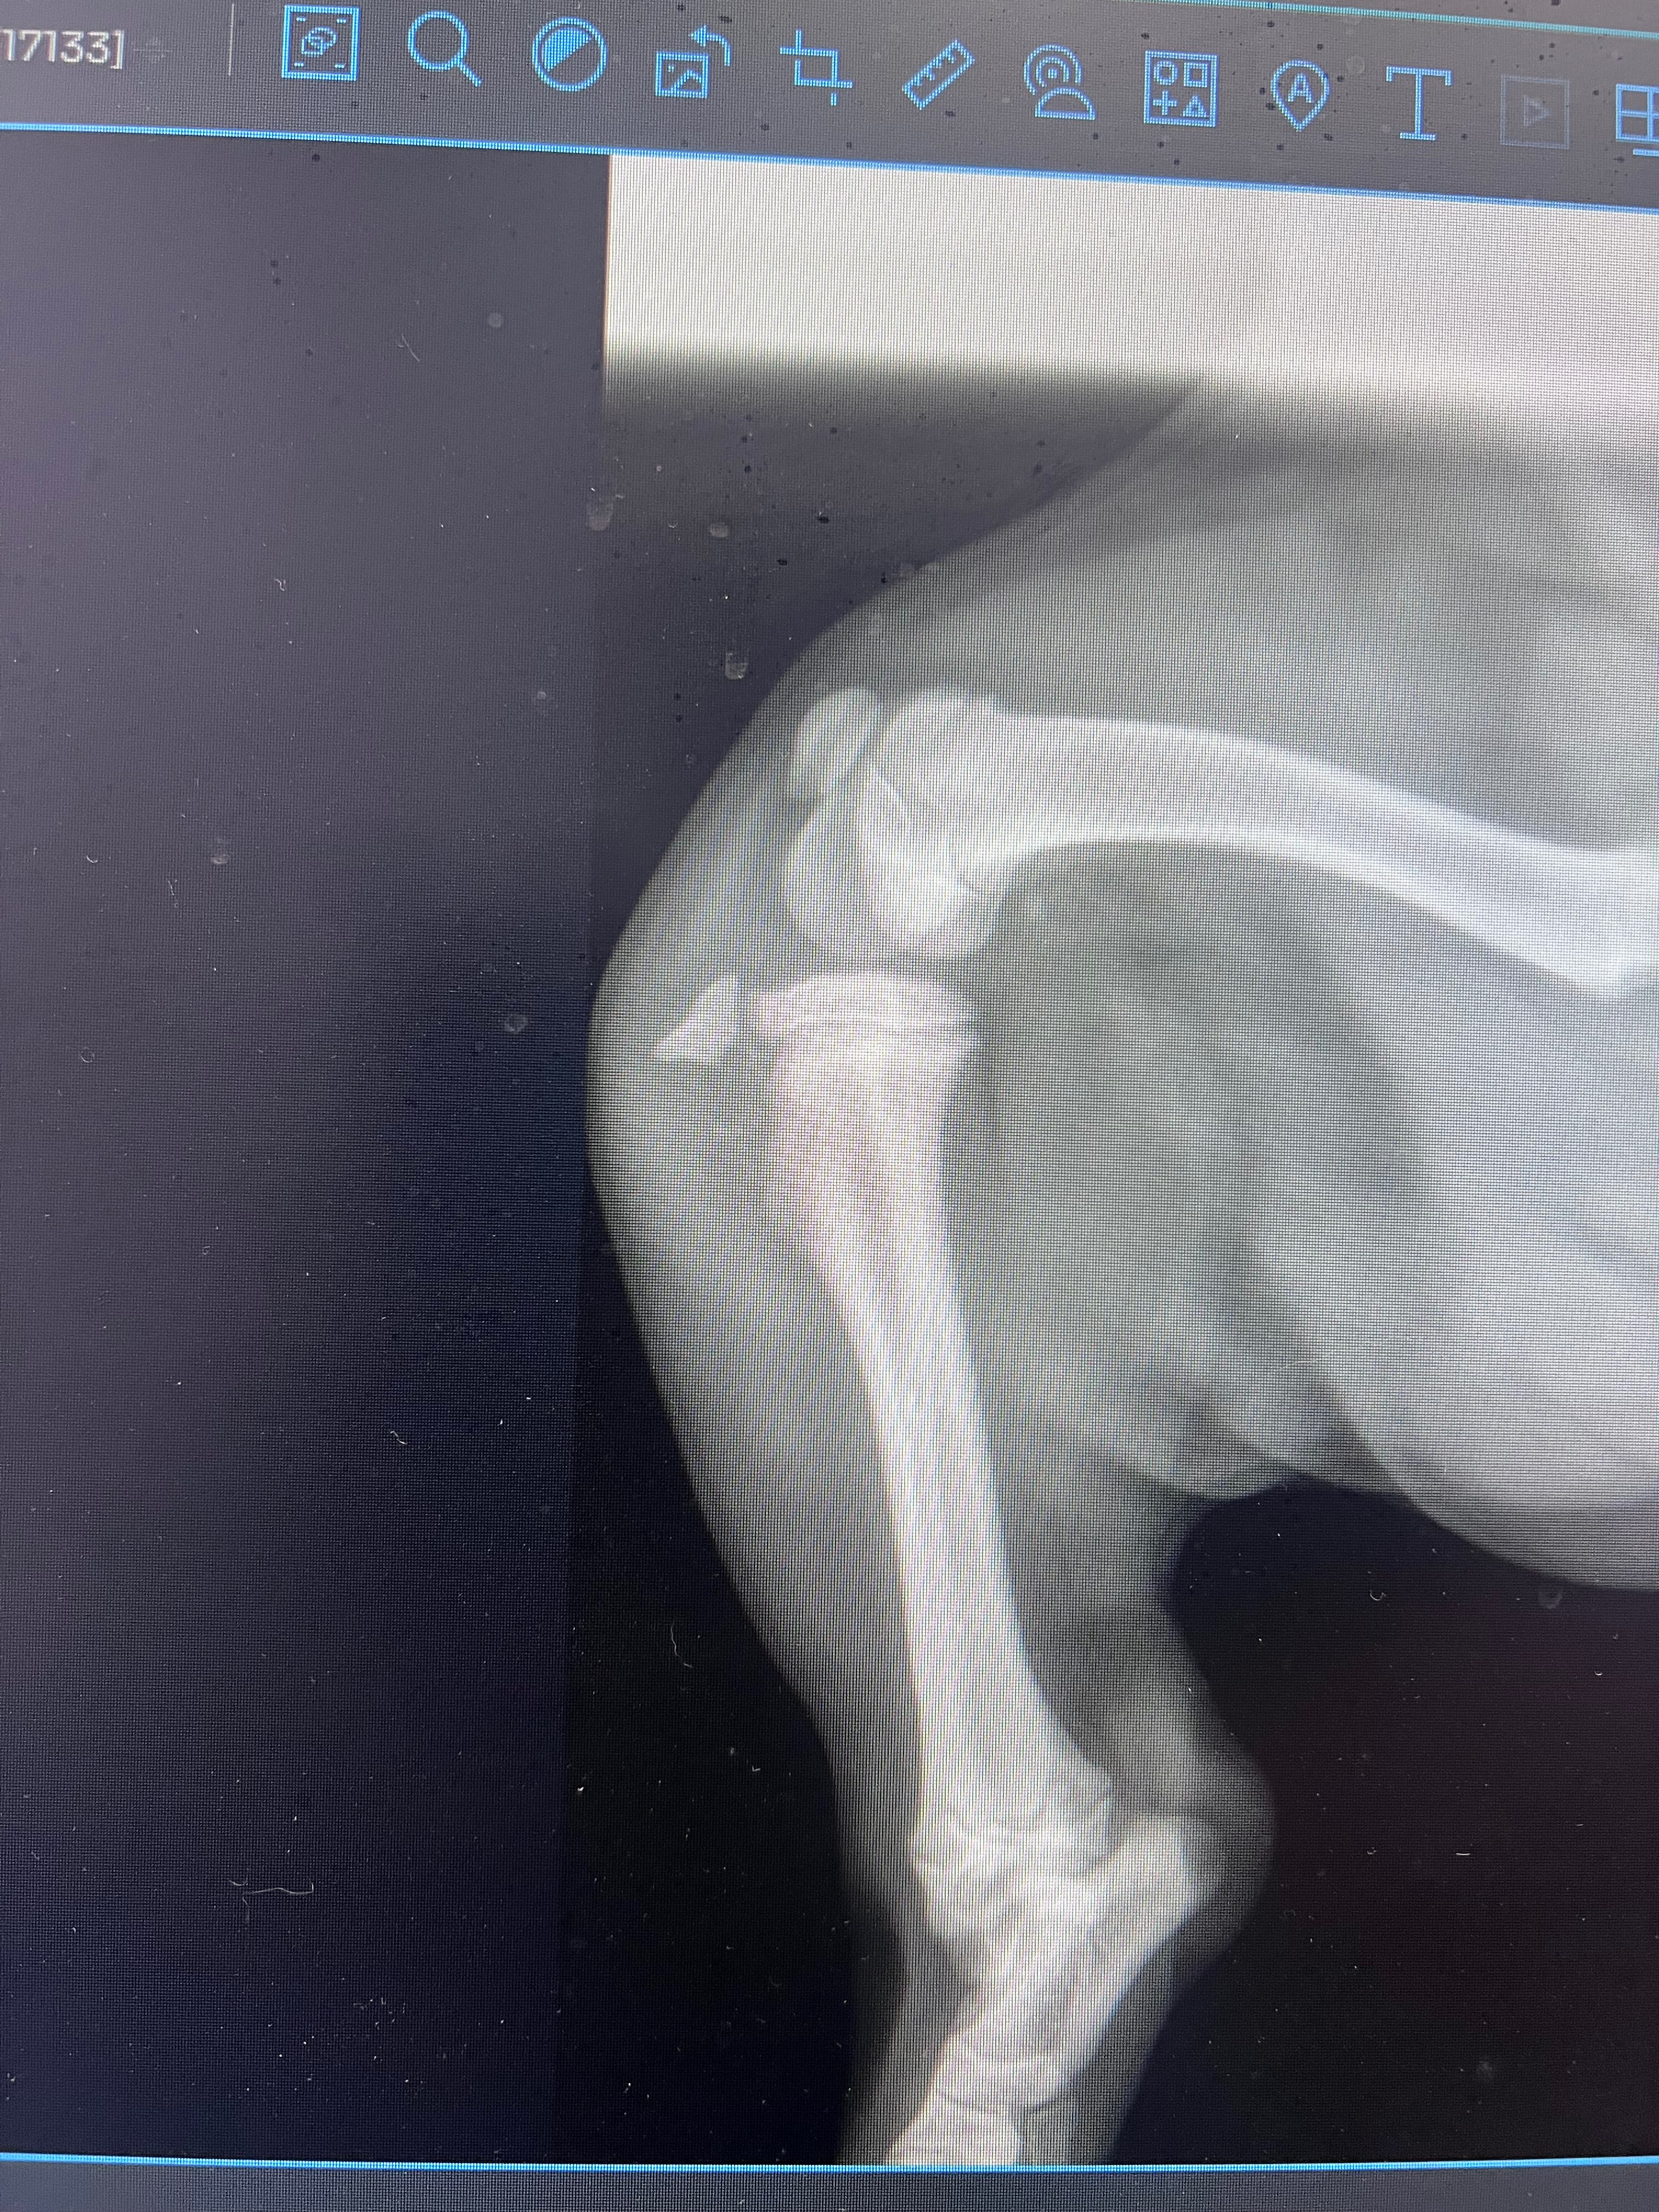

Capone is a 19-week-old puppy with a loving, playful spirit who brings so much joy to my life. Recently, Capone had a fall that left him unable to use his leg, and after a visit to the vet, he was diagnosed with a tibial tuberosity avulsion. The only way for him to recover and get back to his energetic self is through surgery, along with pain medication to help him heal comfortably.